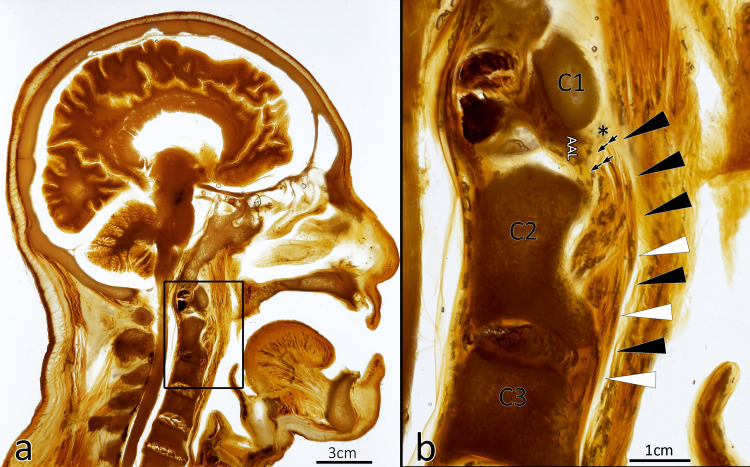

圖2:咽后膿腫和口咽感染的路徑。

圖中整體切面位于C1椎體水平(見標(biāo)注)。咽喉感染有可能穿破咽后筋膜(RF)、咽后間隙(RS)和翼狀筋膜(*),進(jìn)入危險(xiǎn)區(qū)域(DS)(1a)。另一方面,口咽感染可能排入位于咽后間隙側(cè)面的咽后淋巴結(jié)(RPLN);感染隨后可能穿破翼狀筋膜形成危險(xiǎn)間隙的膿腫(?)。從危險(xiǎn)間隙,感染可以向下傳播(2)至后縱隔(☆)(3)。圖中還標(biāo)注了咽后壁(PX)、咽后脂墊(FP)、椎前筋膜(PVF)、顱底(C0)。